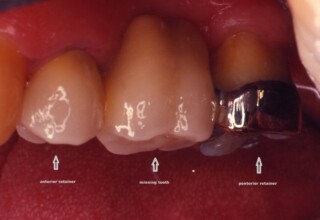

Ακίνητη αποκατάσταση με συνδυασμό κλασσικού και τύπου δακτυλίου συγκρατήματος.

Η απώλεια του άνω προγομφίου αποκαταστάθηκε με μια ακίνητη γέφυρα. Το πρόσθιο στήριγμα ήταν ήδη αποκαταστημένο με στεφάνη οπότε μια κλασσική στεφάνη αποτέλεσε το πρόσθιο συγκράτημα. Το οπίσθιο στήριγμα ήταν ένα ακέραιο, ασφράγιστο δόντι με εκτεταμένη υφίζηση ουλών. Για να αποφευχθεί ο εκτεταμένος τροχισμός και η πιθανή απονεύρωση του δοντιού χρησιμοποιήθηκε ένα συγκράτημα τύπου μεταλλικού δακτυλίου το οποίο προσφέρει ικανοποιητική συγκράτηση από το 2008.